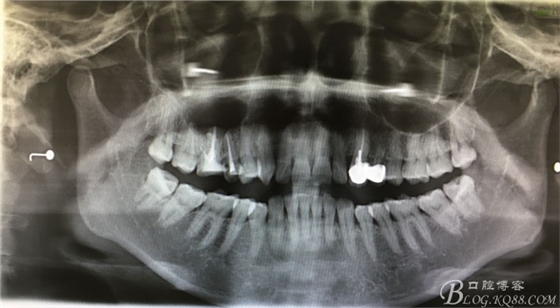

圖3.根尖片顯示15、16根管治療已經(jīng)完成,16腭根牙膠尖超填,15、16根尖區(qū)橢圓形陰影

圖4.全景片影像檢查:以16為中心的橢圓形陰影,當(dāng)時(shí)15未作根管治療。